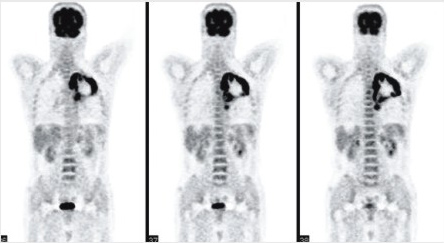

18F-FDG鑒別腫瘤良惡性的局限性

18F-FDG對部分分化程度較高的惡性腫瘤及一些良性病變(如活動(dòng)性結(jié)核病灶、急性炎癥、炎性假瘤)的診斷可能會(huì)出現(xiàn)部分假陰性或假陽性。